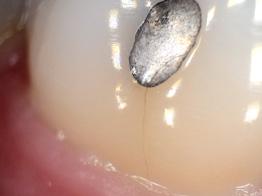

Today, approximately 40% to 50% of dental offices use digital intraoral scanning, and this percentage is only expected to grow.1 Current systems include a scanner with the head created to fit within the oral cavity to capture files of the entire dentition. The files can be used to create restorations as well as appliances either within the dental office or via a lab. While digital intraoral scanning once focused solely on restorative needs, the opportunities for its use have expanded to applications in orthodontics and pathologies such as caries, erosion, and oral cancer. In modern dental practices, this technology can also be integrated into the dental hygiene appointment.1-4

Dental hygienists independently utilize digital scanning for education and motivation. Not only can the clinician educate the patient with the images, but the patient has a visual that is easily understood. These images contain powerful visuals of attrition, fractured teeth, abfraction, gingival recession, overjet, and crowding.4 Biofilm can be displayed after the application of disclosing solution.5 Separate photos are not required to capture the biofilm present when using digital scanning.